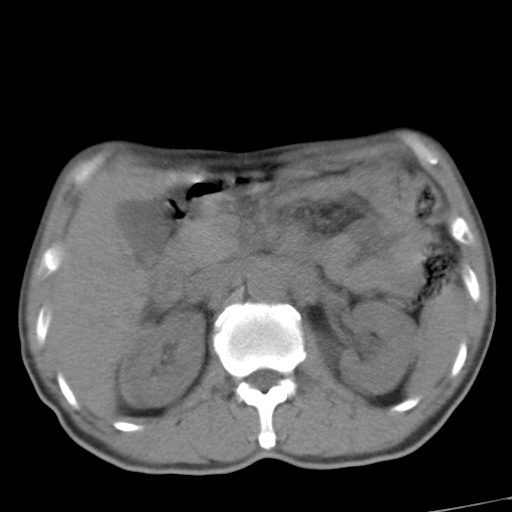

肝脏多发类圆形低密度影,考虑肝脏转移瘤,肝胃韧带一淋巴结肿大,原发?胃癌?

考虑胃癌并肝脏及腹膜后淋巴结转移;不排除淋巴瘤。

肝内转移瘤,腹腔及腹膜后淋巴结转移。